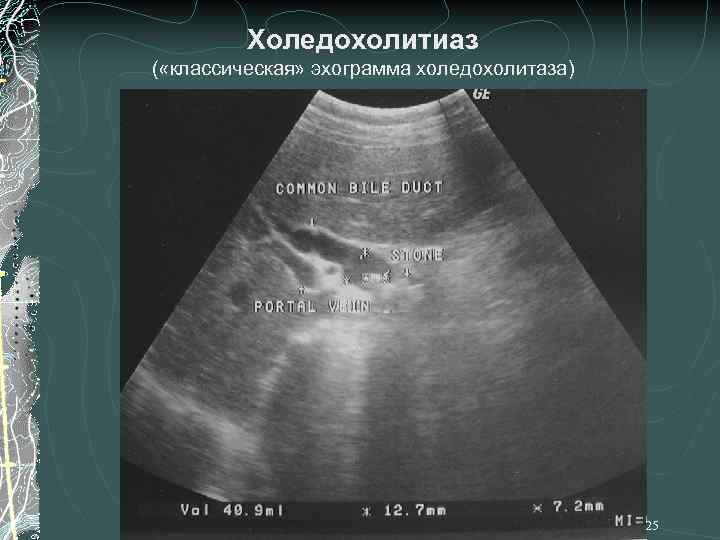

Холедохолитиаз ( «классическая» эхограмма холедохолитаза) 25